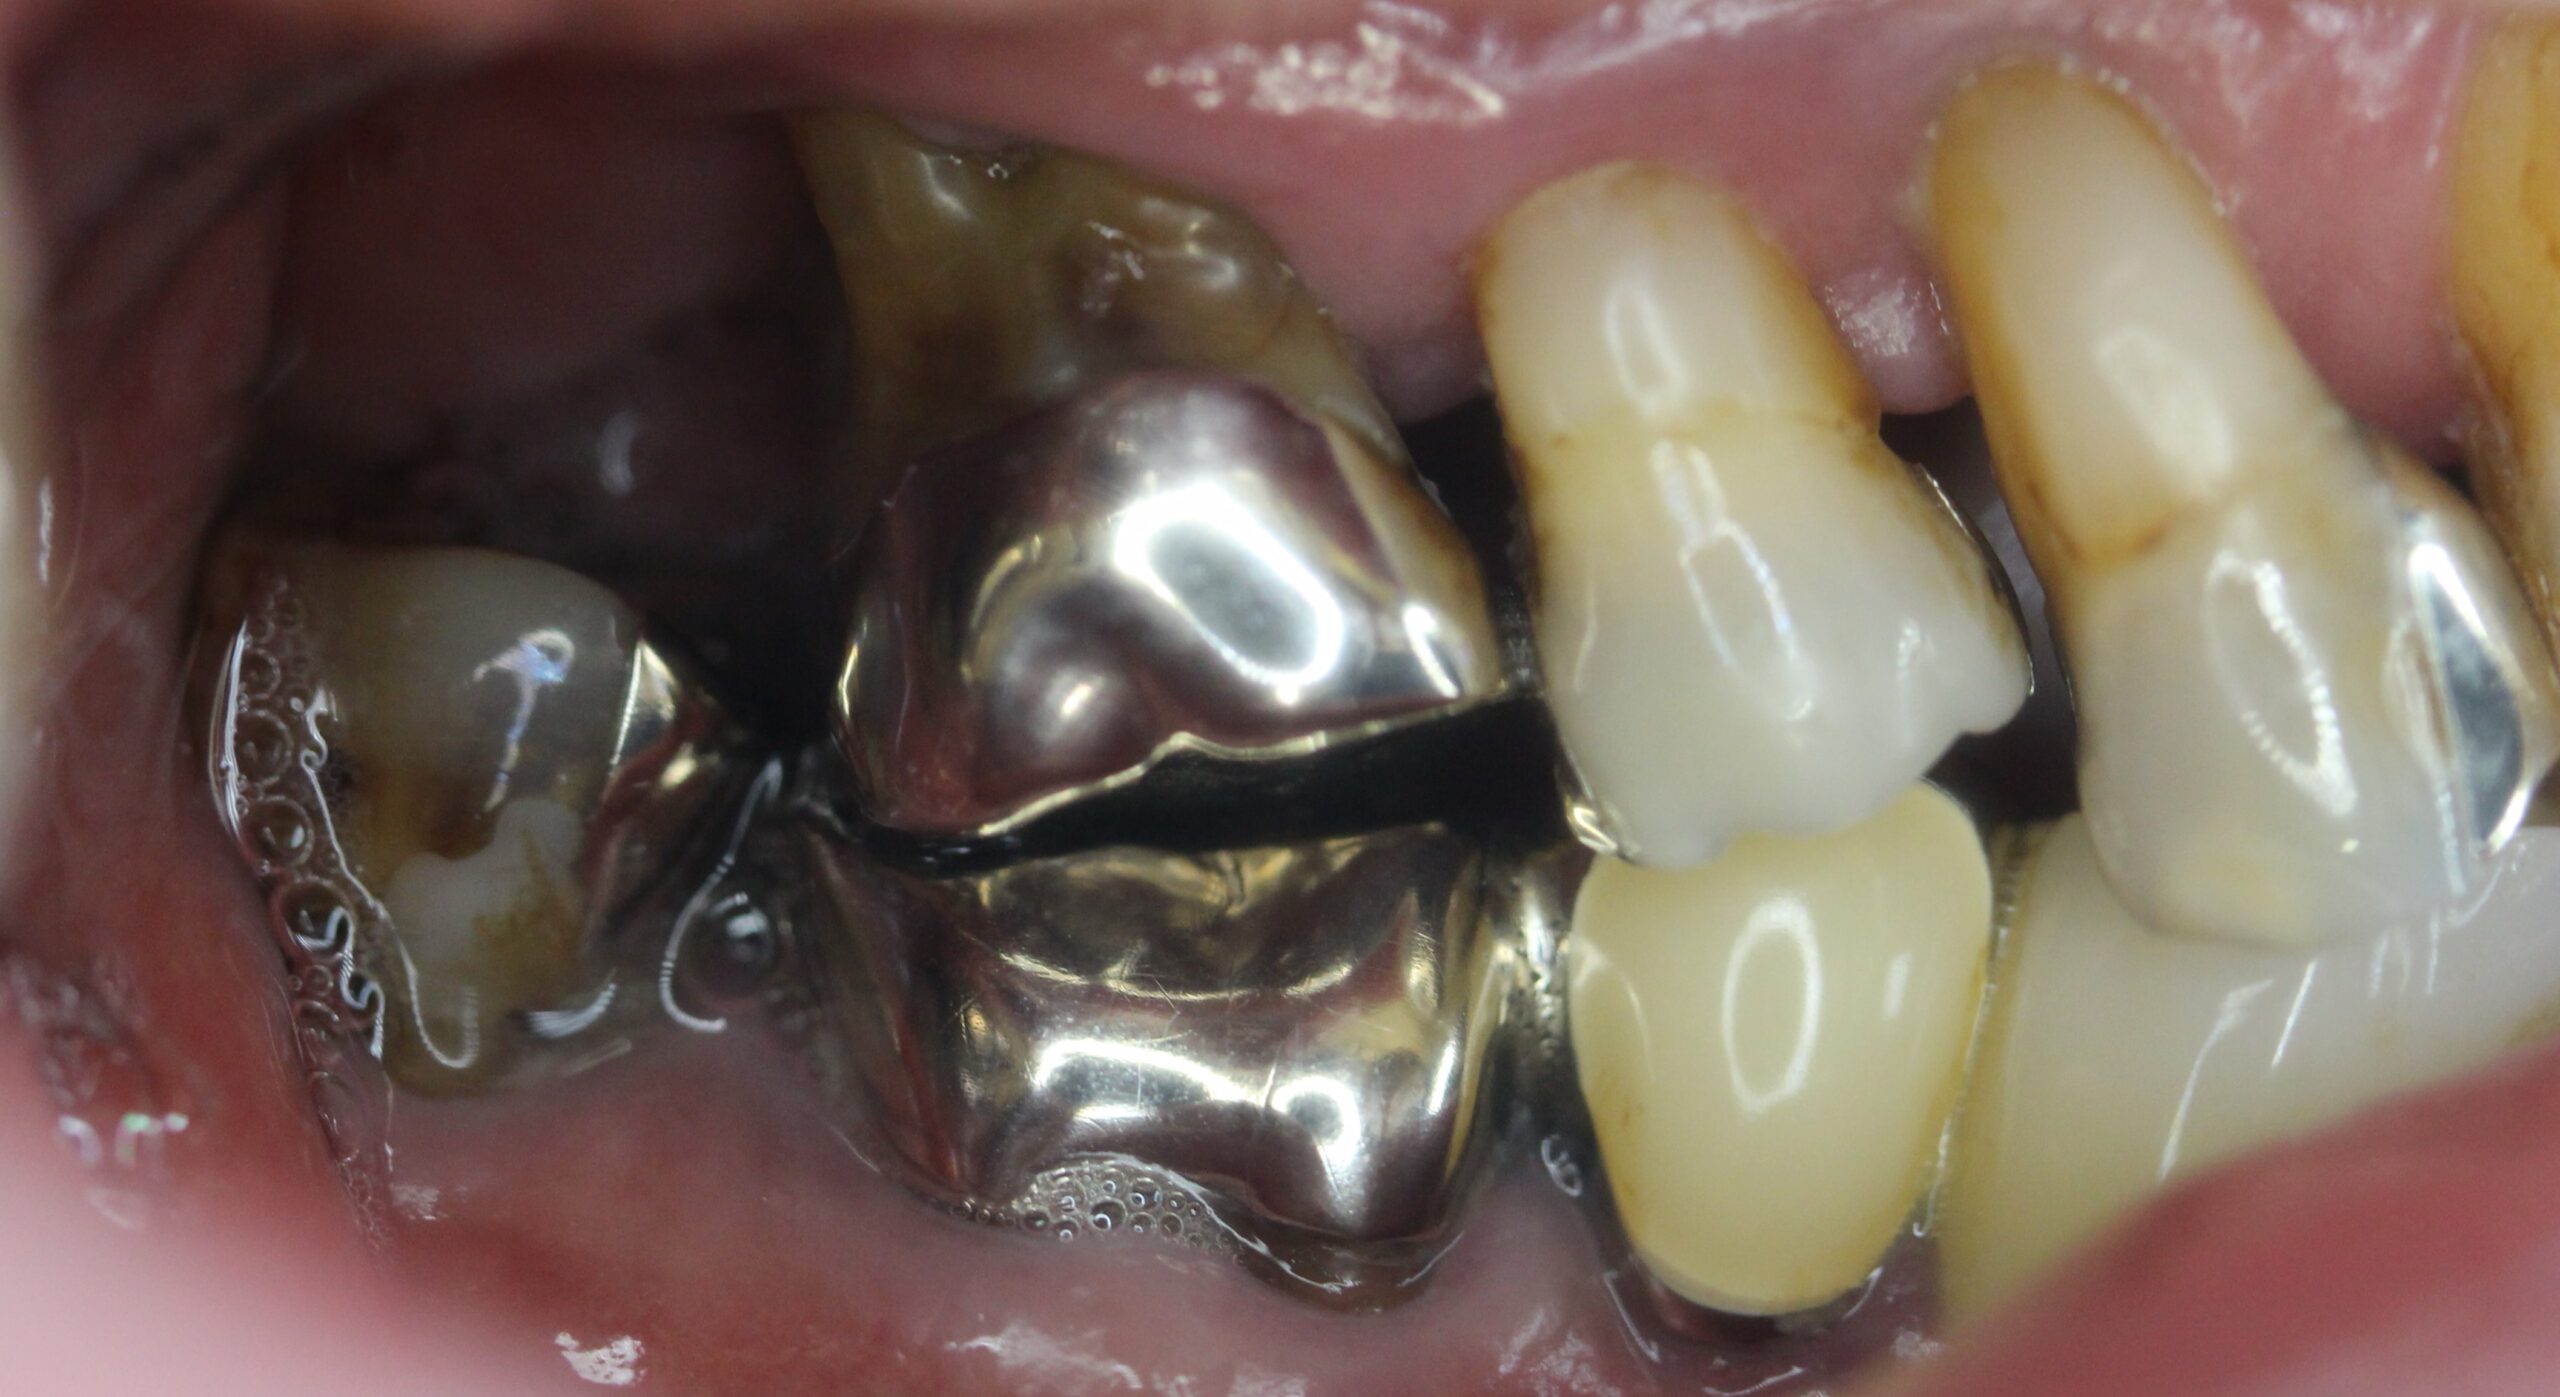

上顎はコーヌステレスコープ、下顎はレジリエンツテレスコープにて治療を行なった。

【治療前】